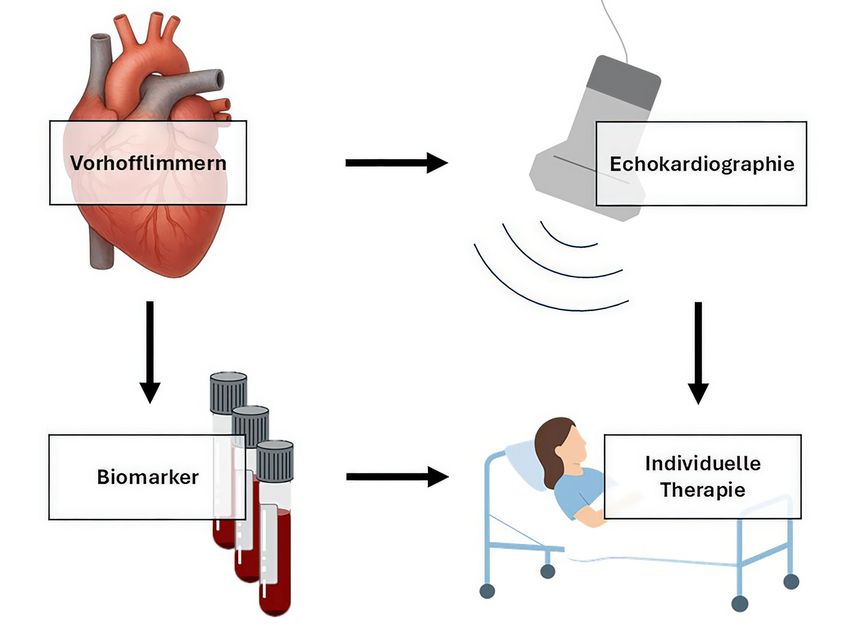

Um den Diagnoseweg zu erleichtern und eine adäquate Versorgung gewährleisten zu können, haben wir uns mit GDF-15 als Biomarker beschäftigt, um das individuelle Risiko unserer Patient:innen besser abschätzen zu können (Abb. 1). Zu diesem Zweck haben wir die Verbindung von GDF-15 und dem linksatrialen Strain in der transthorakalen Echokardiografie untersucht.

Abb. 1: Biomarker und Echokardiografie als wichtige Mittel zur effektiven individuellen Therapie des Vorhofflimmerns